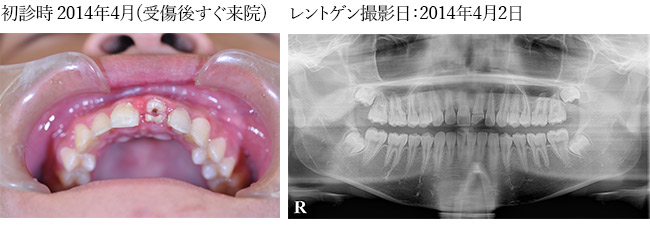

з—ҮдҫӢпј‘

еӨ–еӮ·гҒ«гӮҲгӮҠжӯҜеҶ дҝ®еҫ©еҫҢгҖҖзҹҜжӯЈз”ЁгғҜгӮӨгғӨгғјгҒ«гҒҰеӣәе®ҡ

гҒқгҒ®еҫҢгҖҖжӯҜж №з ҙжҠҳгӮ’иө·гҒ“гҒ—з–јз—ӣгӮ’зҷәз”ҹгҒ—гҒҹгҒҹгӮҒгӮ„гӮҖгҒӘгҒҸжҠңжӯҜгҖӮ

гҒ•гӮүгҒ«гҒқгҒ®еҫҢгҖҖгӮӨгғігғ—гғ©гғігғҲгҒ«гӮҲгӮҠдҝ®еҫ©гҒ—гҒҹз—ҮдҫӢ

иҮӘи»ўи»ҠгҒ§гҒ®дәӨйҖҡдәӢж•…гҒ«гӮҲгӮҠеүҚжӯҜжү“ж’ІгҖҒз ҙжҠҳ

жӯҜеҶ дҝ®еҫ©

е·ҰдёҠпј‘з•ӘжӯҜеҶ дҝ®еҫ©еҫҢгҖҖеӣәе®ҡ

еӣәе®ҡеҫҢжӯҜж №з ҙжҠҳгҒ«гӮҲгӮҠз—ӣгҒҝгҒҢгҒ§гҒҰгҒҚгҒҹгҒ®гҒ§гҒ”жң¬дәәж§ҳгҒ«дәҶи§ЈгӮ’гҒЁгӮҠ

гӮ„гӮҖгҒӘгҒҸжҠңжӯҜгҒ—гҒҹгҖӮгҒқгҒ®еҫҢгҖҖгӮӨгғігғ—гғ©гғігғҲжІ»зҷӮгҒ«гӮҲгӮҠдҝ®еҫ©гҒ—гҒҹгҖӮ

иЎ“еҫҢ

| в‘ жІ»зҷӮеҗҚ | дәӨйҖҡдәӢж•…гҒ«гӮҲгӮӢеүҚжӯҜз ҙжҠҳгҖӮгӮӨгғігғ—гғ©гғігғҲгҒ«гӮҲгӮӢдҝ®еҫ© |

|---|---|

| в‘ЎиІ»з”Ё | гӮёгғ«гӮігғӢгӮўгҒ«гӮҲгӮӢеүҚжӯҜдҝ®еҫ©пјҲгӮөгғјгӮёгӮ«гғ«гӮ¬гӮӨгғүдҪҝз”Ёз—ҮдҫӢпјүпј“пјҗдёҮеҶҶпјҸжң¬ |

| в‘ўжңҹй–“ | пј“жңҲпј‘пјҳж—ҘжҠңжӯҜгҖҒпј–жңҲпј‘пјҷж—ҘгӮӘгғҡгҖҒпјҷжңҲпј’пјҳж—ҘTEKгӮ»гғғгғҲгҖҒпј‘пјҗжңҲпј‘пј‘ж—ҘгӮёгғ«гӮігғӢгӮўгӮ»гғғгғҲгҖҖе®ҢдәҶгҒҫгҒ§зҙ„пј—гҒӢжңҲ |

| в‘ЈйҖҡйҷўй »еәҰ | гӮӘгғҡеҫҢгҒҜзҝҢж—Ҙжҙ—жө„гҖҒпј‘йҖұй–“еҫҢиҰіеҜҹгҖҒгҒ•гӮүгҒ«пј‘йҖұй–“еҫҢжҡ«й–“зҫ©жӯҜгҒ®зўәиӘҚгҖҒиӘҝж•ҙгҖҒпј‘гҒӢжңҲеҫҢзўәиӘҚгҖҒжё…жҺғгҖҒгҒӮгҒЁпј‘гҒӢжңҲгҒ”гҒЁгҒ«зўәиӘҚгҖҒпјҷжңҲгҒ«PTVгҒ«гҒҰгӮӘгӮ№гғҶгӮӘгӮӨгғігғҶгӮ°гғ¬гғјгӮ·гғ§гғігҒ®зўәиӘҚгҖҒеҚ°иұЎгҖҒTEKиЈ…зқҖгҖҒзҙ„пј’йҖұй–“еҫҢгҖҖгӮёгғ«гӮігғӢгӮўгӮ»гғғгғҲ |

| в‘ӨжӮЈиҖ… | пј’пјҗд»ЈгҖҖеҘіжҖ§ |

| в‘ҘжІ»зҷӮеҶ…е®№ | иҮӘи»ўи»ҠгҒЁи»ҠгҒ®дәӨйҖҡдәӢж•…гҒ§еүҚжӯҜгӮ’жү“ж’ІгҖҒи…«и„№гҖӮжҡ«й–“еӣәе®ҡгҒ§еӣәе®ҡгҒ§гҒҚгӮӢгҒҢжӯҜж №з ҙжҠҳгҒ®гҒҹгӮҒж №з®ЎжІ»зҷӮгӮ’гҒҠгҒ“гҒӘгҒЈгҒҹгҒҢз ҙжҠҳз·ҡгҒҢеәғгҒҢгӮҠжҠңжӯҜгӮ’дҪҷе„ҖгҒӘгҒҸгҒ•гӮҢгҒҹгҖӮиӢҘгҒ„еҘіжҖ§гҒ§гҒӢгҒӨеүҚжӯҜпј’жң¬гҒ®гҒҹгӮҒгӮёгғ«гӮігғӢгӮўдҝ®еҫ©гӮ’гҒҷгӮӢгҒ“гҒЁгҒ«гҒӘгҒЈгҒҹгҖӮ |

| в‘ҰжІ»зҷӮзөҗжһң | еҜ©зҫҺзҡ„гҒ«гӮӮж©ҹиғҪзҡ„гҒ«гӮӮжӮЈиҖ…гҒ•гӮ“гҒ”жң¬дәәгҒҢжәҖи¶ігҒ§гҒҚгӮӢзөҗжһңгҒЁгҒӘгҒЈгҒҰгҒҠгӮҠе®ҡжңҹжӨңиЁәгӮ’гҒҠйЎҳгҒ„гҒ—гҒҰгҒ„гӮӢгҖӮ |

| ⑧注ж„ҸзӮ№ | еүҚжӯҜгҒ®гҒҹгӮҒеҜ©зҫҺзҡ„гҒ«гӮӮж©ҹиғҪзҡ„гҒ«гӮӮеӣ°гӮүгҒӘгҒ„гӮҲгҒҶгҒ«гӮөгғјгӮёгӮ«гғ«гӮ¬гӮӨгғүгӮ’дҪҝз”ЁгҒ—гҒҹгҖӮгҒ“гӮҢгҒ«гӮҲгӮҠиЎ“еүҚгҒ«жӮЈиҖ…гҒ•гӮ“гҒ«дәҲжё¬гӮ’иҰӢгҒҰгҒ„гҒҹгҒ гҒҸгҒ“гҒЁгҒҢгҒ§гҒҚе®үеҝғгҒ«гӮӮгҒӨгҒӘгҒҢгҒЈгҒҹгҒЁиҖғгҒҲгҒҰгҒ„гӮӢгҖӮгҒ„гҒҫгҒ®гҒЁгҒ“гӮҚеӨ§дёҲеӨ«гҒ§гҒҷгҒҢгӮ№гӮ№гӮҜгғӘгғҘгғјеӣәе®ҡгҒ®зӮәдёҮгҒҢдёҖиў«гҒӣгҒ®гӮёгғ«гӮігғӢгӮўгҒ«гғҲгғ©гғ–гғ«гҒҢзҷәз”ҹгҒ—гҒҰгӮӮдҝ®зҗҶгҒҷгӮӢгҒ«гҒҜжҜ”ијғзҡ„е®№жҳ“гҒЁжҖқгӮҸгӮҢгӮӢгҖӮ |